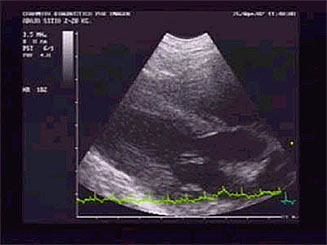

En el modo B y en el corte para-esternal derecho de

4 cámaras en eje largo, se observó una

cardiomegalia generalizada con prominencia del ventrículo

y atrio derechos (la sobrecarga de volumen ventricular

causa una dilatación diastólica ventricular

sin afectación del grosor de la pared, "dilatación

excéntrica" y función sistólica

normal). |